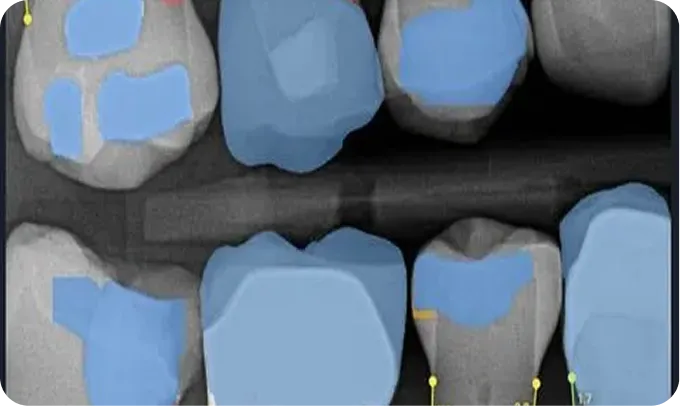

AI without findings

AI activated, showing Decay in red, and Yellow lines indicate bone loss